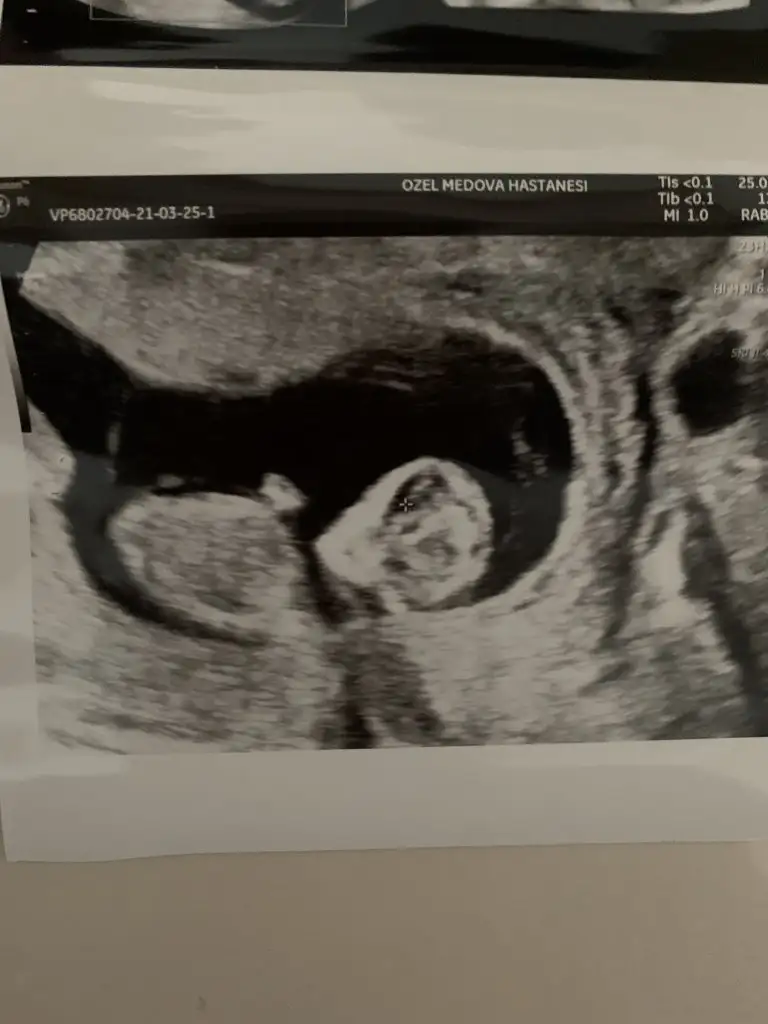

Canım Ikra meyra Ikra meyra bu arada sen kız dedikten sonra iyice inceledim ve 3 çizgi gördüm 🤗 aşağıda işaretledim. Yalnız internette bakarken erkek 3 çizgisinde bizimki gibi birinin ayrık gibi olduğunu gördüm. Sence son kararın ne 😌 kız mı erkek mi? Söz bir daha rahatsız etmeyeceğim seni 🤗

Eklentiler

• 0CC59AD4-FF92-466E-8859-5AEC5EFCE8F4.webp

0CC59AD4-FF92-466E-8859-5AEC5EFCE8F4.webp

8,2 KB · Görüntüleme: 94

• BFBC3871-CC42-4A8B-A5BB-45DB1AB25BB2.webp

BFBC3871-CC42-4A8B-A5BB-45DB1AB25BB2.webp

26,2 KB · Görüntüleme: 95

Senin bebek kız görünüyor tipide kız gibi